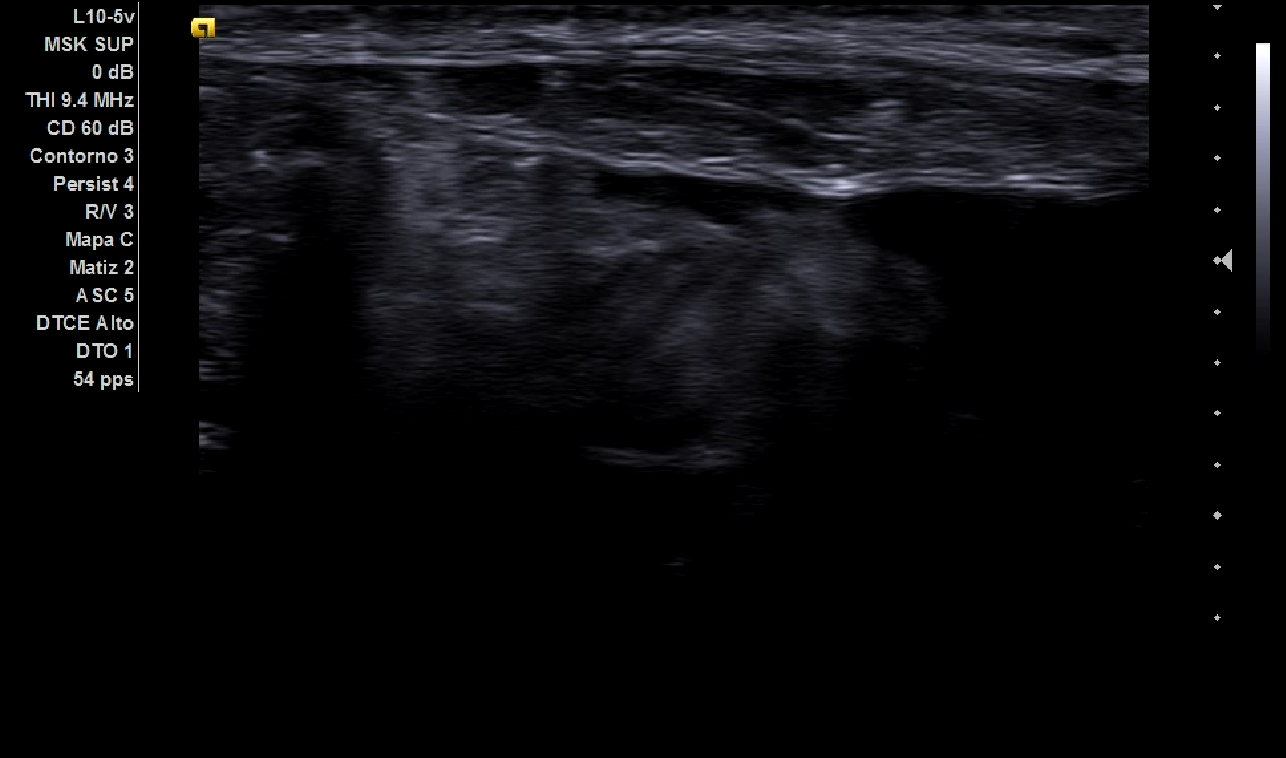

Al realizar la ecografía se aprecia masa heterogénea, móvil, con cordón espermático en la superficie (imagen 1), destacando que en el escroto había abundante contenido hipoecoico compatible con hidrocele. Todos ellos hallazgos compatibles con hernia inguinal de grandes dimensiones.

La hernia inguinal es un diagnóstico que puede realizarse sin apenas uso de pruebas complementarias, tan solo con una adecuada y sistemática exploración física. Sin embargo, con la llegada de la ecografía a los centros de salud, disponemos de una herramienta fundamental para realizar un primer abordaje de una masa abdominal. En el caso de sospechar una hernia inguinal en un hombre de debe comenzar por situar el transductor en posición transversal sobre el testículo, y se debe buscar el cordón espermático (en la superficie de la imagen 1), siguiéndolo proximalmente al anillo superficial hasta su desaparición en el anillo profundo. Se debe evaluar toda la extensión de la hernia, rastreando hasta su origen. Tener en cuenta que si se localiza lateralmente a la arteria epigástrica inferior es una hernia indirecta; de lo contrario, es directa. También es útil evaluar el Doppler para cerciorarnos de que el asa puede ser viable.